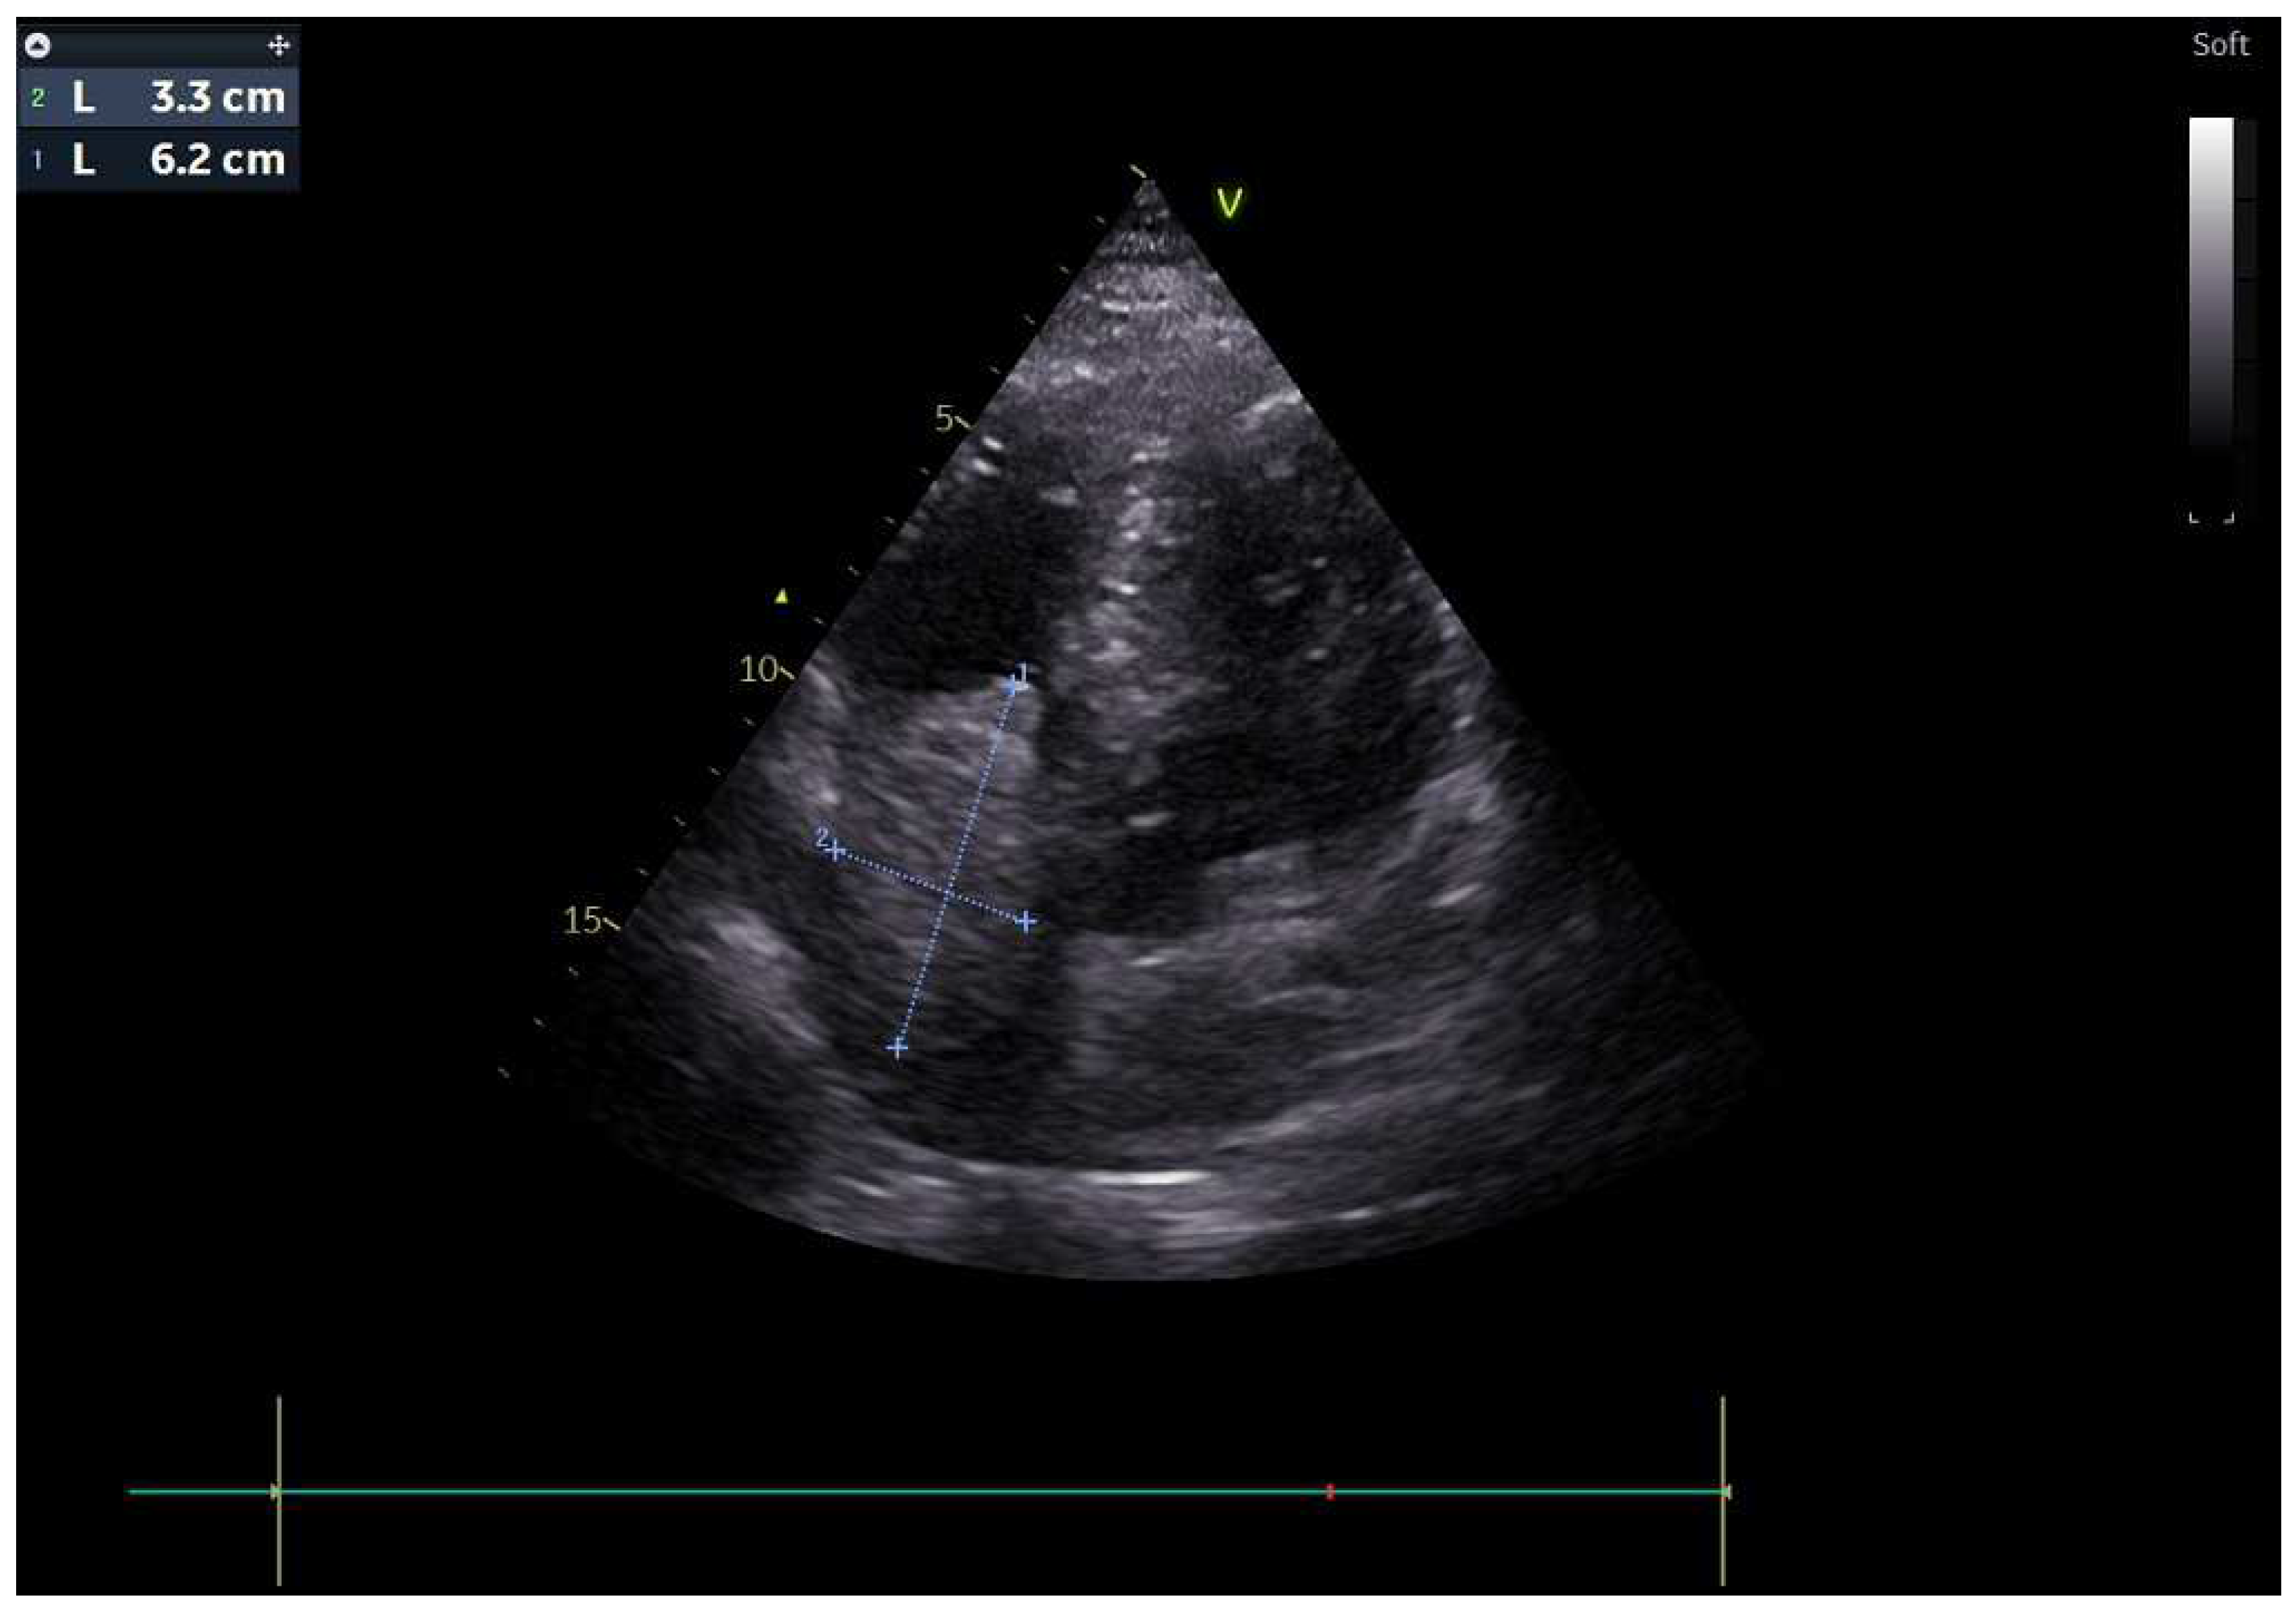

A 51-year-old male patient presented to our clinic in December 2023 with fatigue, abdominal distension and leg edema, which started three weeks prior. He had no history of chronic disease. On physical examination, dullness in the abdomen upon percussion, suggestive of fluid, was observed. Additionally, there were decreased breath sounds in the basals of the lungs, a tachycardic heart rhythm, and significant pretibial edema. The electrocardiogram (ECG) was consistent with sinus tachycardia. The patient’s blood pressure was 130/90 mmHg. Laboratory tests revealed hemoglobin: 13.2 g/dL; fasting blood glucose: 95 mg/dL; serum creatinine 1.2 mg/dL; aspartate aminotransferase (AST) 49 U/L; alanine aminotransferase (ALT): 46 U/L; bilirubin: 0.69 mg/dL; albumin: 3.6 g/dL; carcinoembryonic antigen (CEA): 43 ng/mL; and carbohydrate antigen (CA) 19-9: 361 U/mL. Electrolyte levels were within normal limits. Urinalysis showed proteinuria of 0.4 g/day. Paracentesis revealed a serum-to-ascites albumin gradient greater than 1.1 g/dL. Cytological examination of the fluid revealed benign cytological findings. TTE revealed a lesion 6.2 × 3.3 cm in diameter, suggestive of a low-moving hypoechoic thrombus or mass (Figure 1). This lesion almost completely filled the right atrium and stuck to the tricuspid valve. Dilation of the inferior vena cava and severe insufficiency of the tricuspid valve were also observed. A work-up was started to differentiate heart failure and a possible cardiac mass. Thorax CT showed multiple nodules in the lung and a suspicious mass in the right atrium. A PET scan showed that there was segmental wall thickening at the stomach and esophagogastric junction, measuring 7.5 cm in size and showing 18-FDG uptake with an SUV max of 22.4, which was evaluated in favor of primary malignancy. Multiple metastatic lymphadenopathy in the abdomen, free fluid in the abdominopelvic region, metastatic lesions in the liver and lung and supraclavicular lymphadenopathy were detected (Figure 2). The lesion seen on TTE was evaluated as a tumoral thrombus suspicious lesion with dimensions of 8.8 × 5.5 cm at the level of the right atrium on PET-CT and a maximum standard unit value (SUVmax) of 12.8. Cardiac magnetic resonance imaging (CMRI) was planned to differentiate the tumor/thrombus, but it could not be performed because the patient could not tolerate lying flat. Cardiology and surgery opinions were obtained, and close follow-up with anticoagulant treatment was recommended. An ulcerovegetating mass was detected in the upper-GI endoscopic evaluation. Histopathological evaluation of the biopsy specimen was consistent with gastric adenocarcinoma. PD-L1 IHC was conducted using a Ventana Dako anti-human PD-L1 mouse monoclonal antibody, clone 22C3, with a positive control. PD-L1 protein expression was assessed using the CPS and found to be positive, with a value of 15. HER-2 status was evaluated by both IHC and silver in situ hybridization (SISH). For IHC, Ventana anti-HER-2/neu rabbit monoclonal antibody clone: 4B5 was employed with a positive control. SISH was performed on a Ventana Benchmark Ultra fully automated system using the inform HER-2 dual in situ hybridization DNA probe cocktail with positive and negative controls. The HER-2 IHC score was +3, and SISH demonstrated HER-2 gene amplification with a HER-2/CEP17 ratio ≥ 2 (positive).

Figure 2. PET scan showed that there was a tumoral lesion with dimensions of 8.8 × 5.5 cm at the level of the right atrium with SUV max: 12.8.